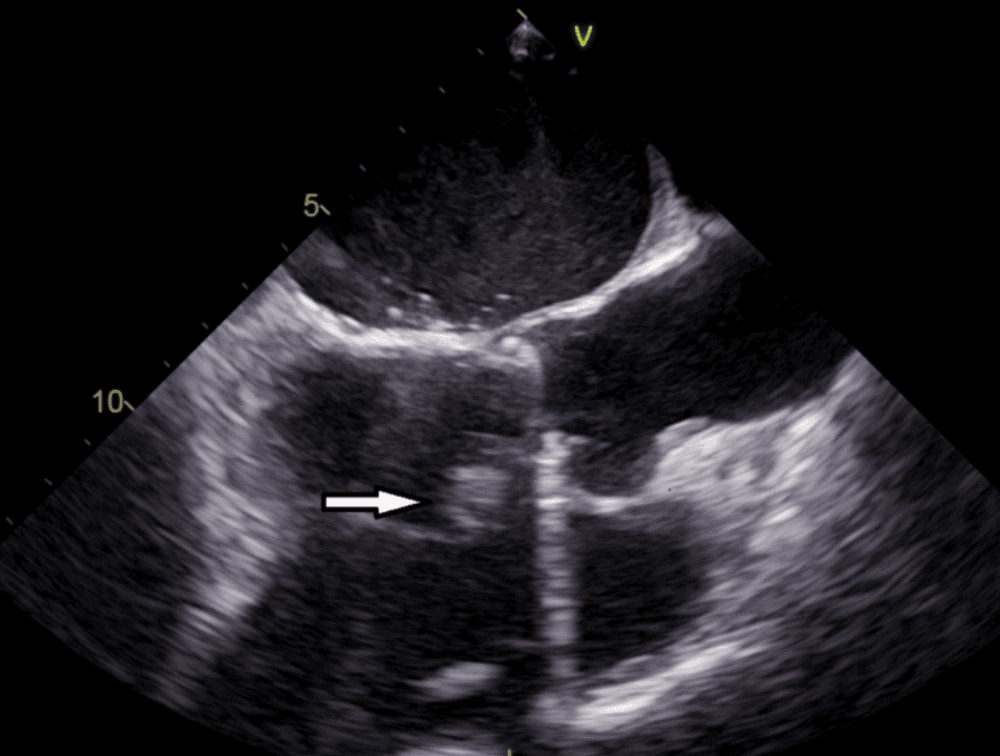

Echocardiogram demonstrating an aortic valve vegetation.

Laboratory studies show a white blood cell count of 8.9 x 10^9/L, hemoglobin 12.6 g/dL, platelets 214 x 10^9/L, C-reactive protein 29 mg/dL, and erythrocyte sedimentation rate 58 mm/hour. Aspartate aminotransferase is 42 U/L and alanine aminotransferase is 39 U/L. Transthoracic echocardiography demonstrates a friable vegetation on the aortic valve with an aortic root abscess. Four blood culture sets remain negative at 48 hours, but one bottle later grows a small gram-negative coccobacillus after prolonged incubation. A standard tube agglutination test returns positive at a titer of 1:640.